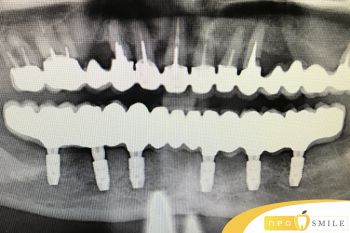

В клинику обратилась пациентка с полным отсутствием зубов нижней челюсти.

Было принято решение на нижней челюсти установить мостовидный металокерамический протез, с искусственной десной (для эстетики).

Пациентке установлено 6 имплантатов на которых был закреплен красивый мостовидный протез из керамики.